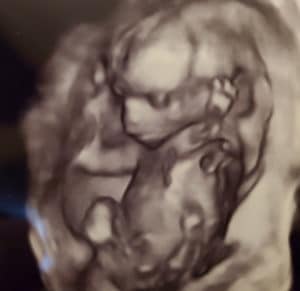

18 Weeks Pregnant After Tubal Reversal Of Tubal Clips!

Reversing Tubal Clips: Expecting A Girl!

18-weeks-pregnant-tubal-reversal-tubal-clipsFirst pregnancy after tubal reversal and we are having a girl.

I am currently 18 weeks pregnant.

Thank you so much Dr. Monteith!

Patient age: 29

Tubal ligation type: Tubal clips (clamps)

Patient hometown: Newport, Michigan